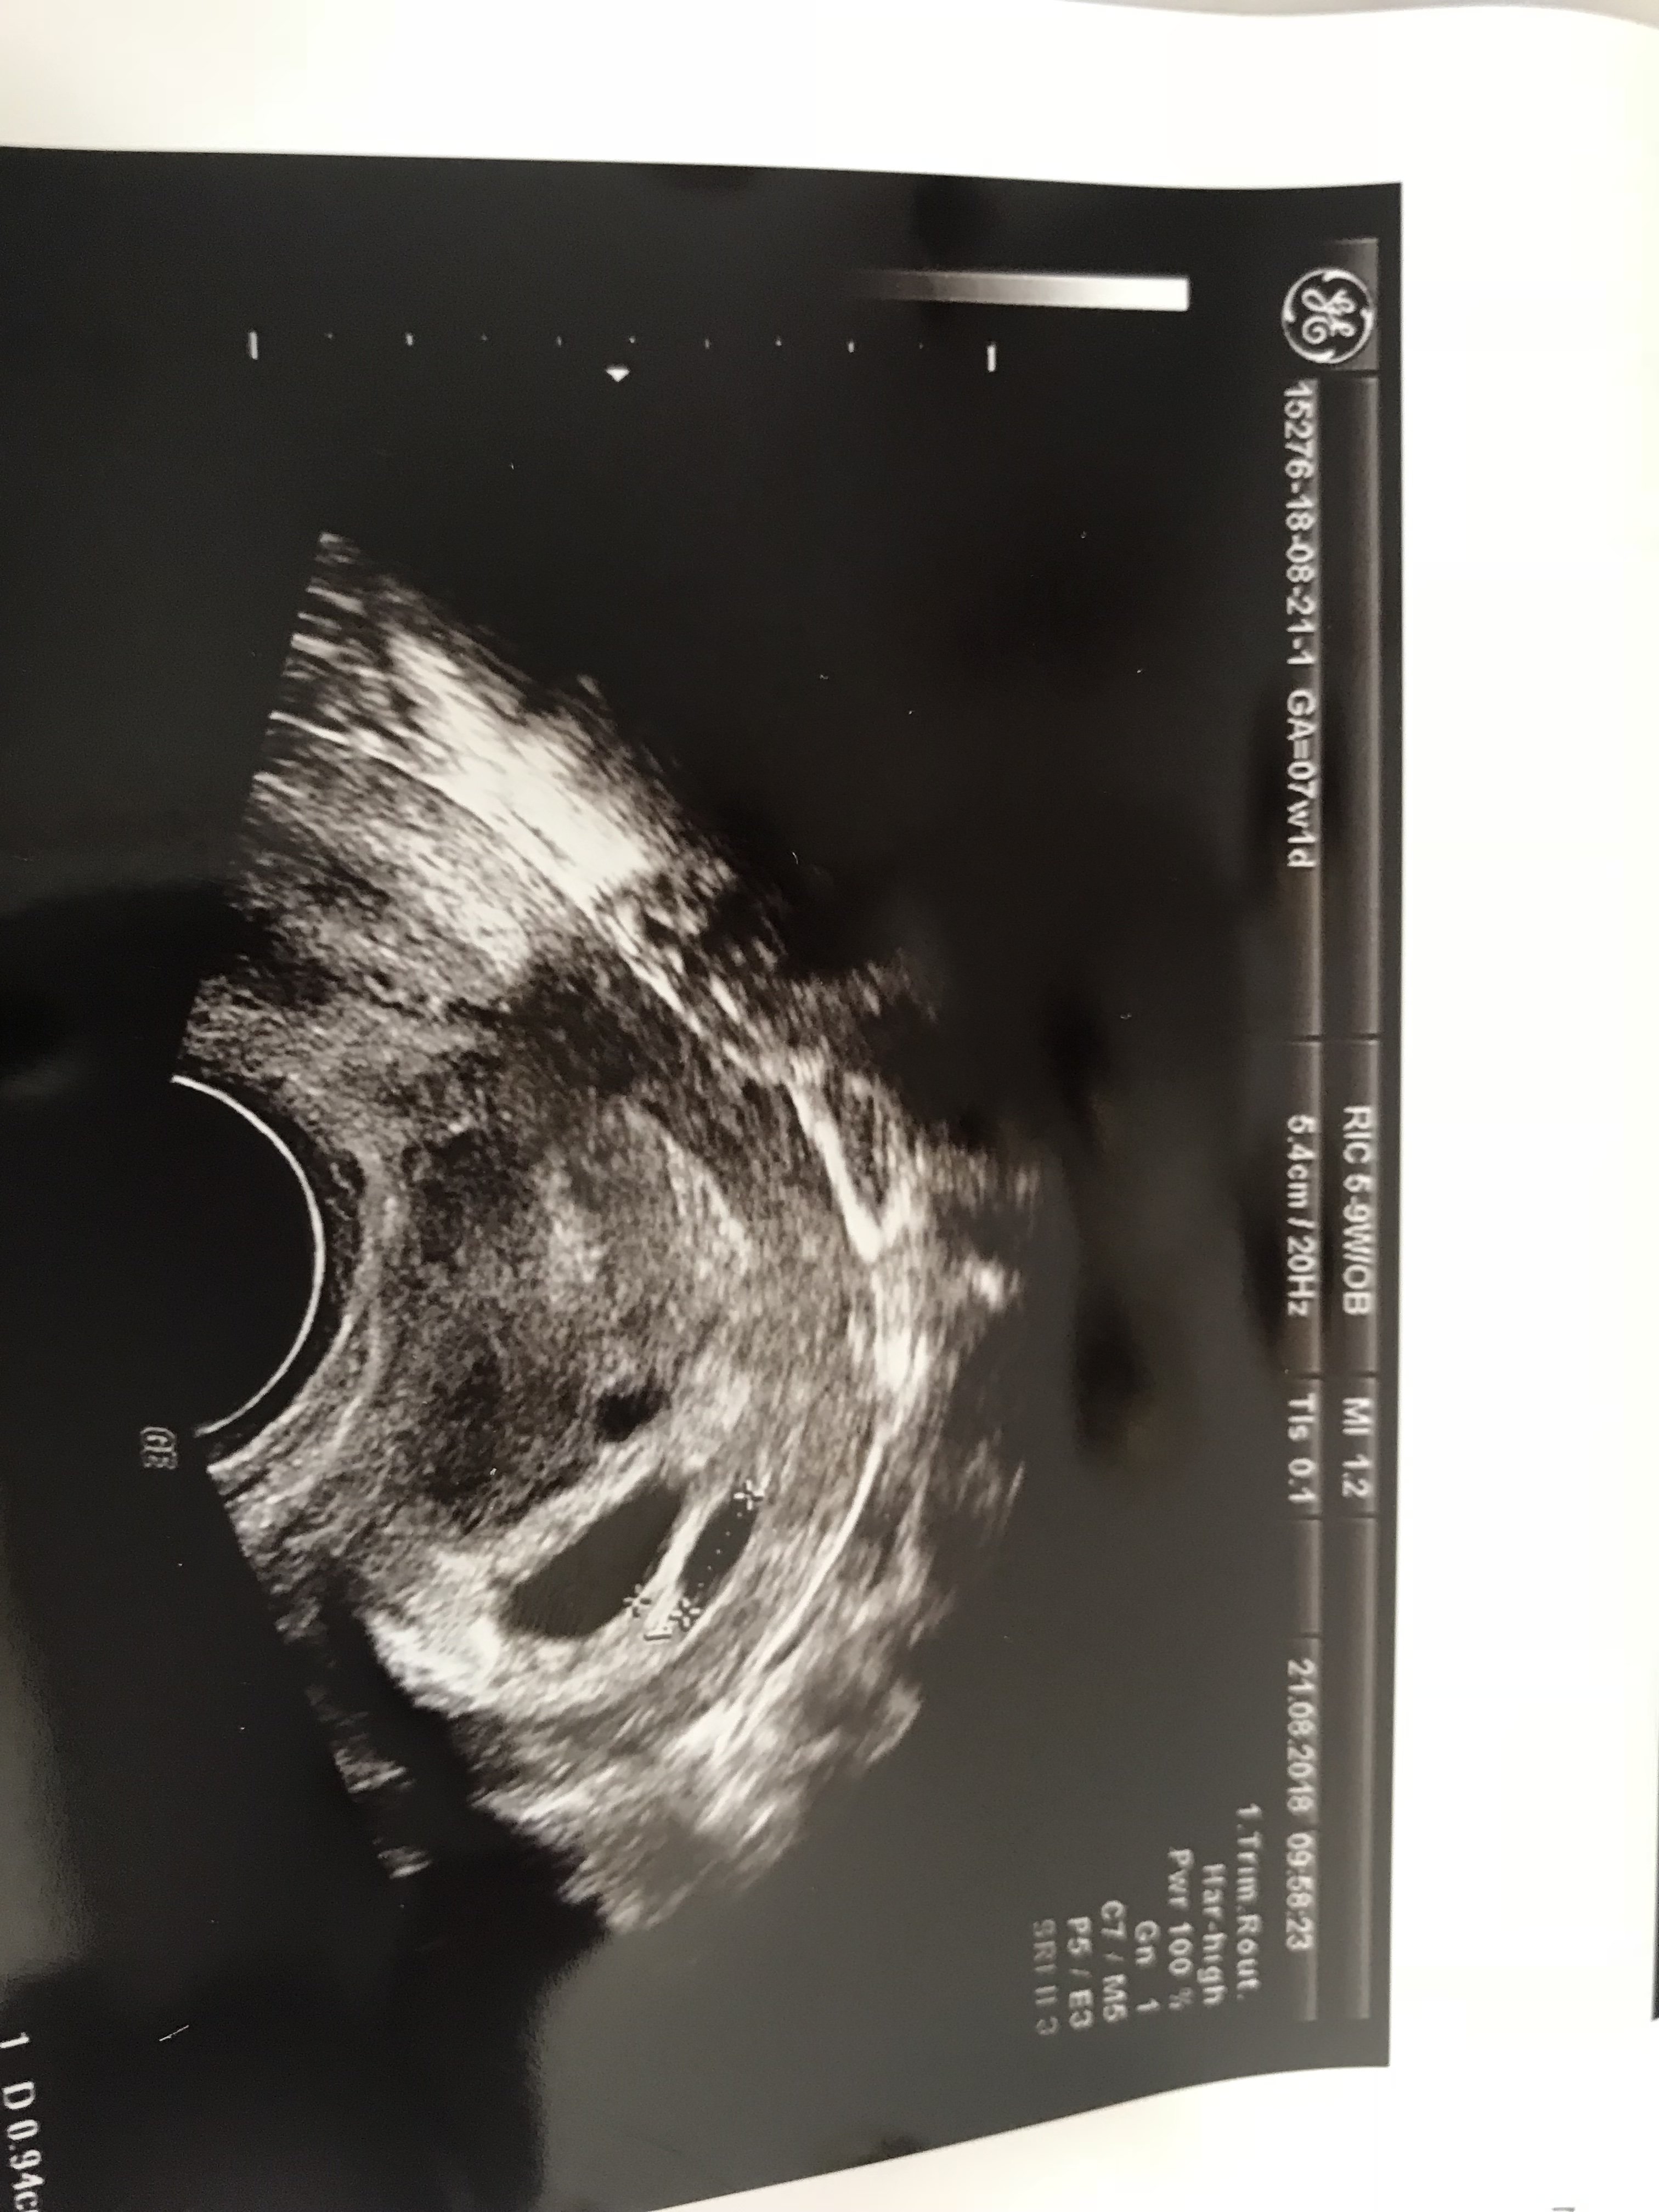

Problem po mojej stronie niedrożny jajkowod drugiego brak to nasza 3 próba i mieliśmy podane tym razem dwa zarodki 2Bb i jeden zdecydował być nasza największa miłościąGratulacjęsuper takie rzeczy słyszeć - budujące jest to dla nas ciąglę walczących. A powiedz mi proszę problem był bardziej po Twojej stronie czy u męża. Jeszcze raz gratuluje